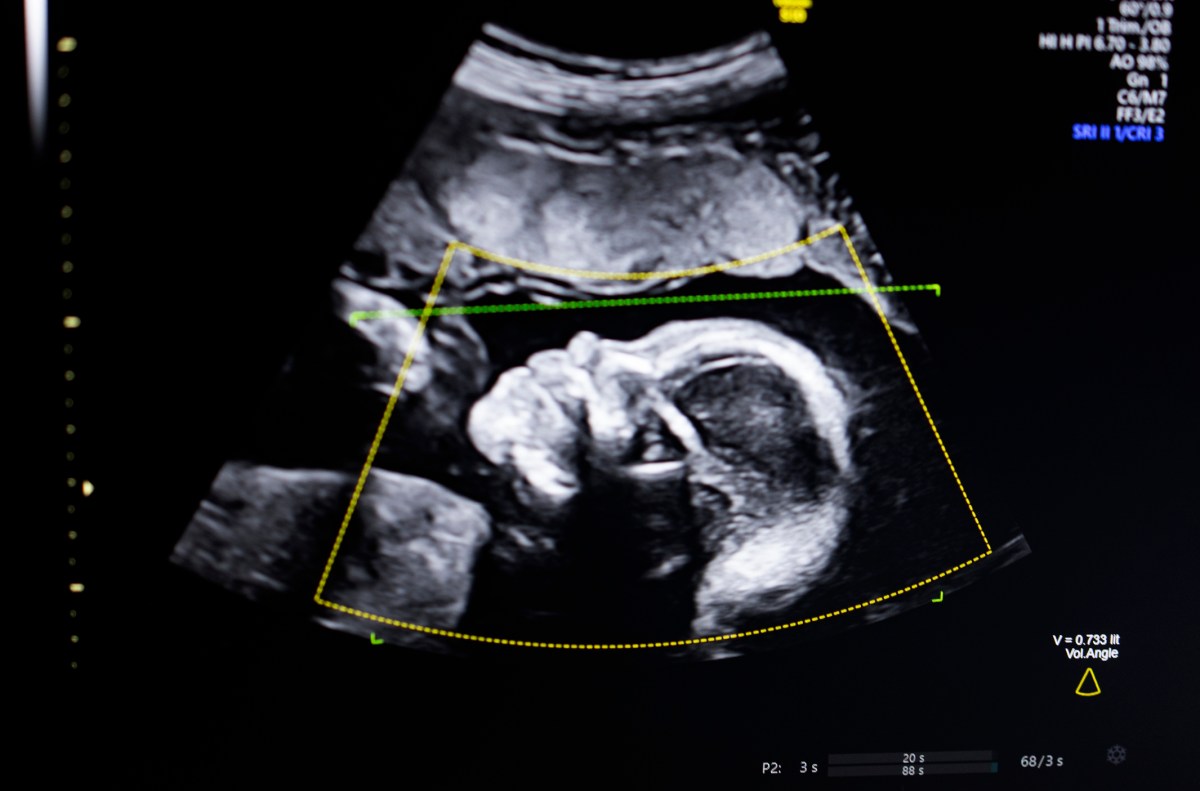

The technology uses computer vision AI “to support fetal ultrasound quality assessment, anatomical completeness, automated reporting, and seamless integration into clinical workflows,” Bustami told TechCrunch.

Bustami said that the prenatal ultrasound has become the “cornerstone” of monitoring pregnancies, but its low-quality images can lead to misdiagnosis.

Bustami said the hardest part was not building his AI models, which were trained on a diverse set of hundreds of thousands of ultrasounds, but ensuring the tech performed reliably in the real world, especially on demographics with the highest risk for a tragic outcome.